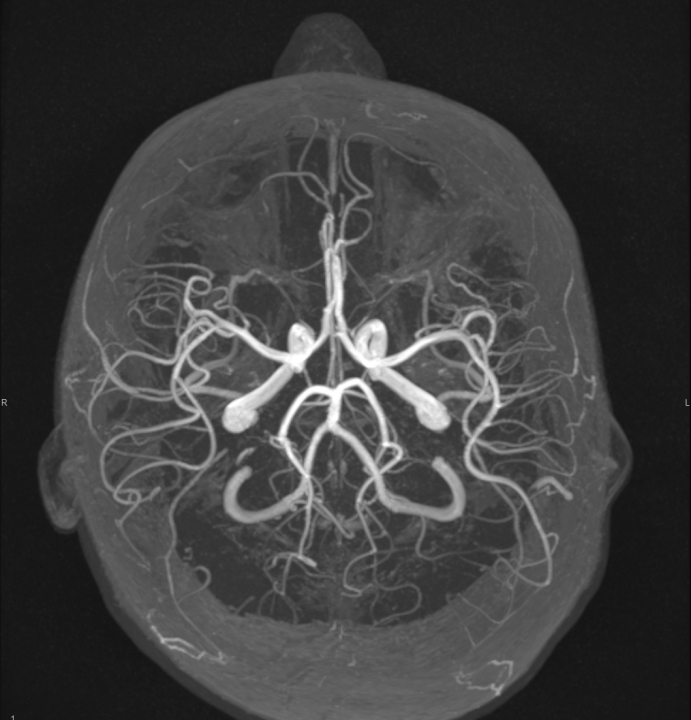

Tijekom Tjedna mozga Poliklinika Affidea Vita daje 20 posto popusta na magnetsku rezonancu!

Povodom obilježavanja Tjedna mozga od 11.